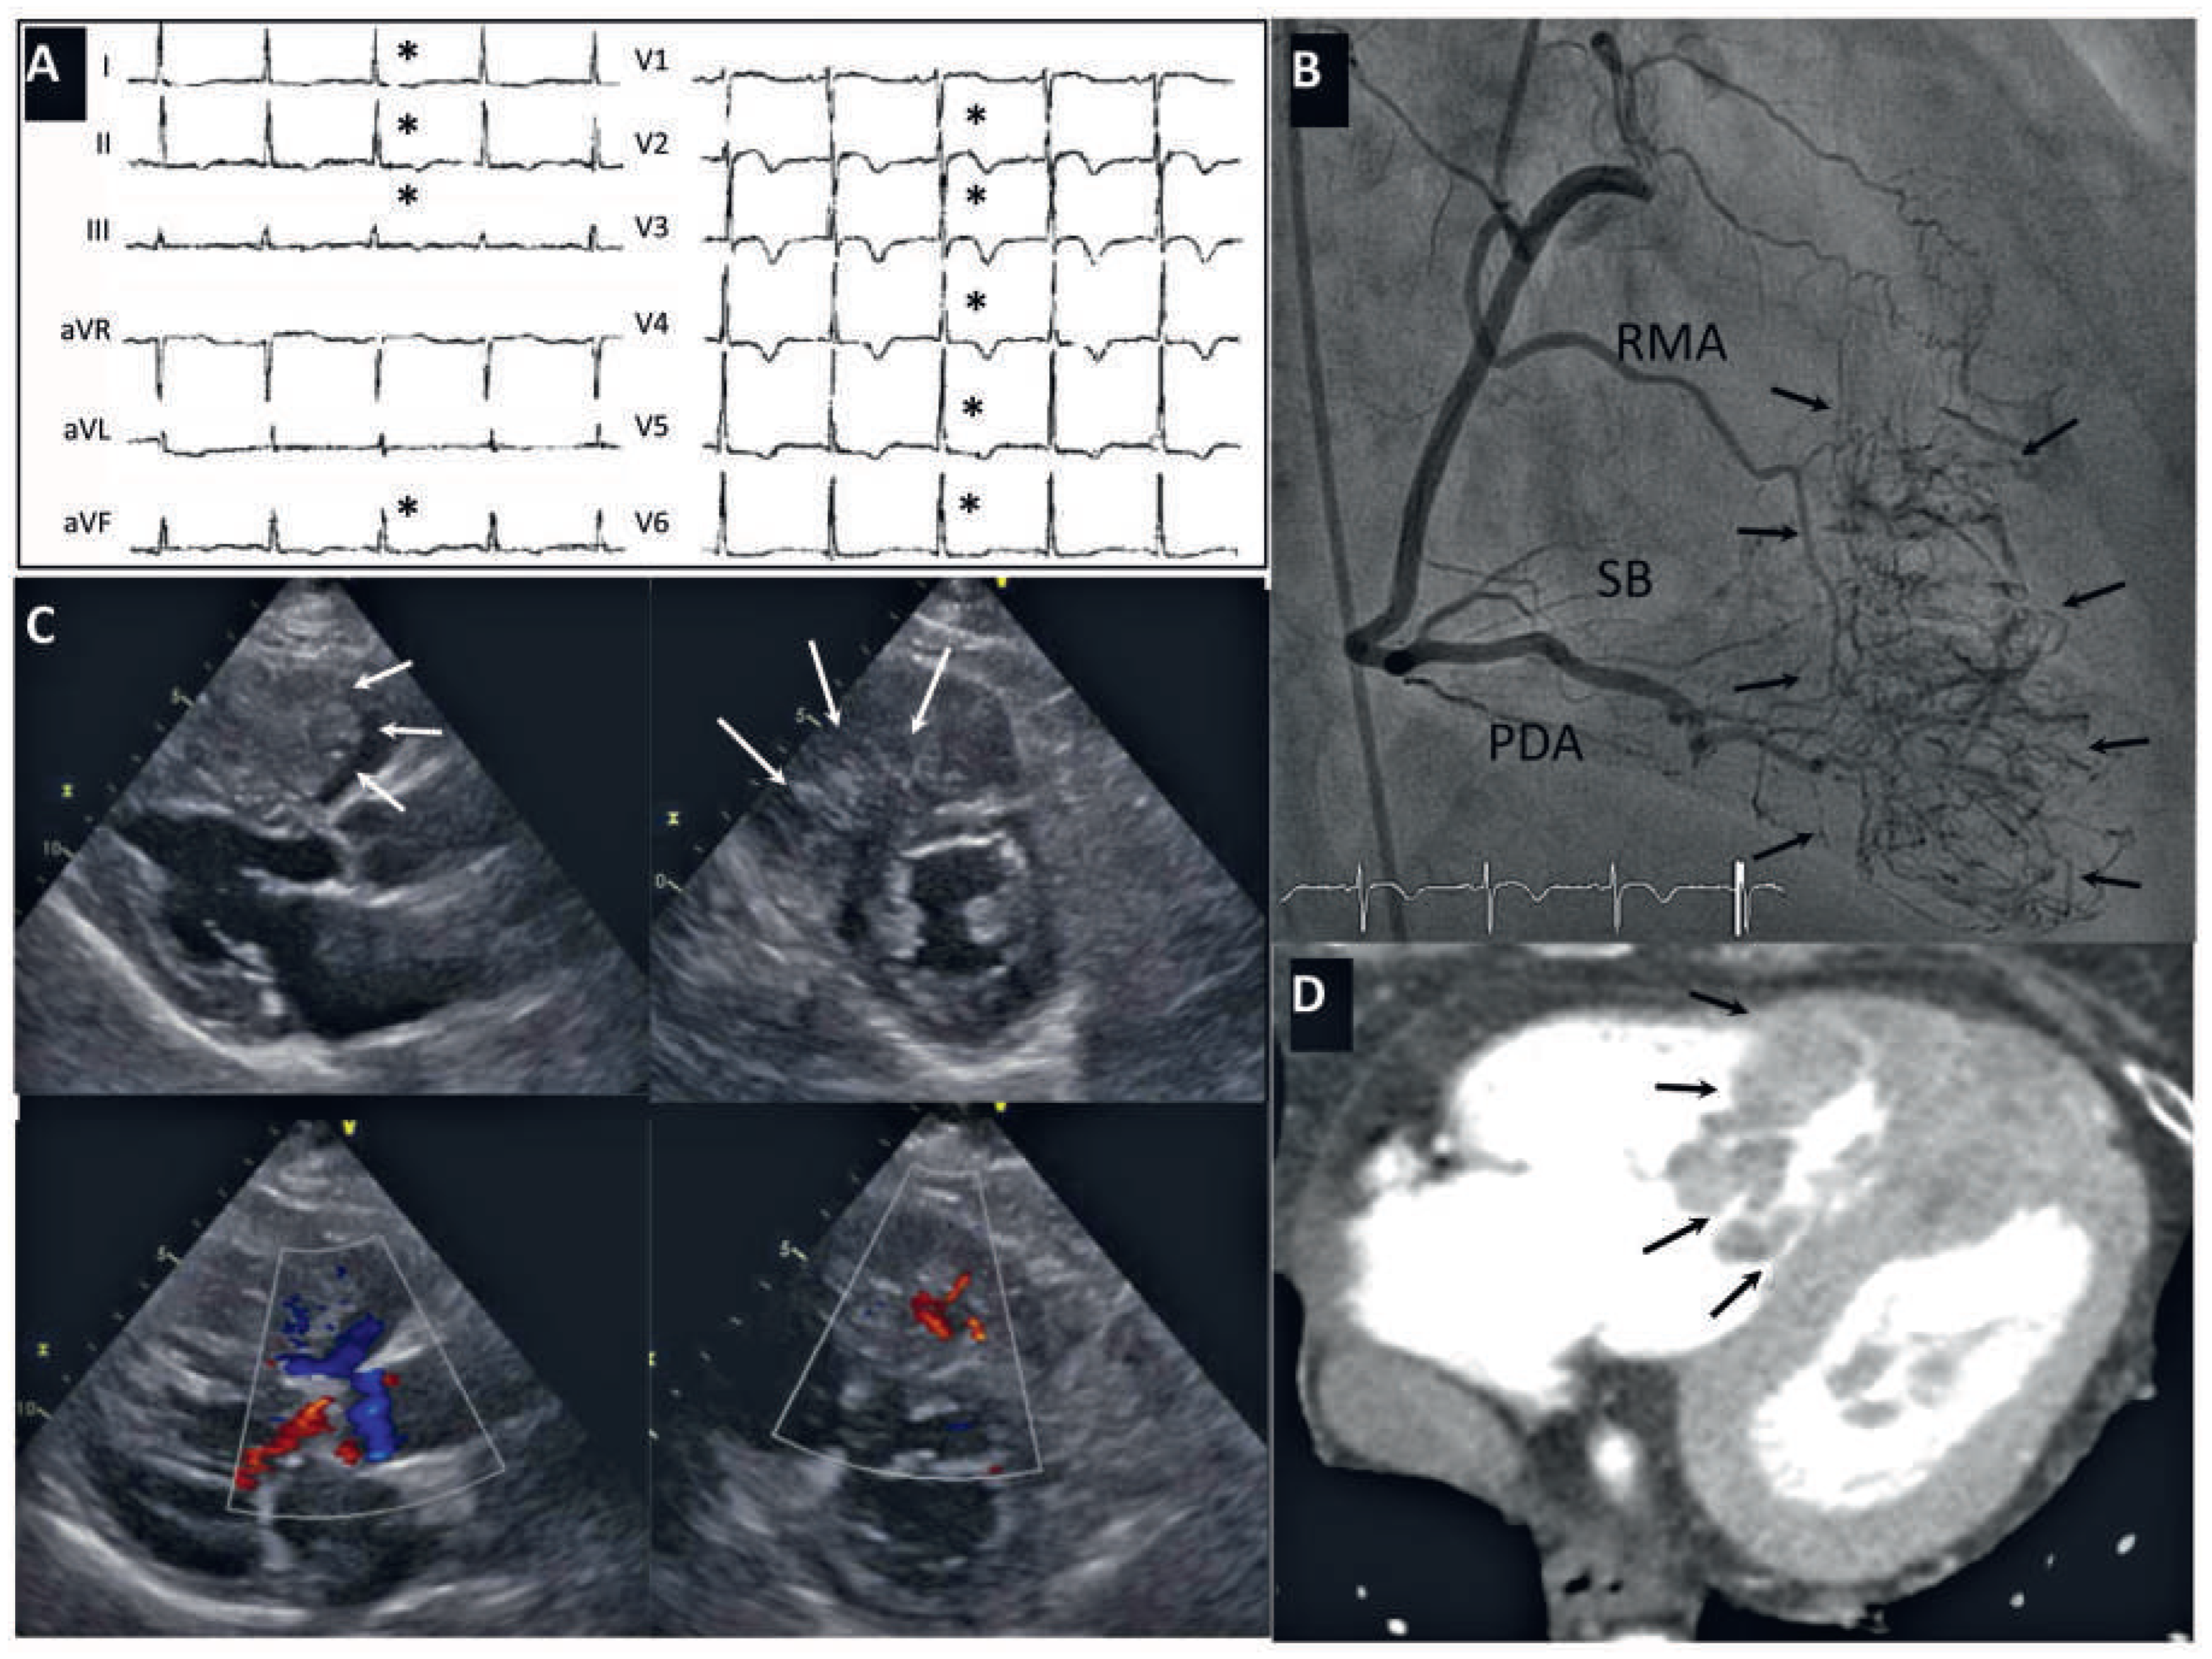

Short Breath, Small Vessels and Big Heart—An Unusual Suspect

Case report